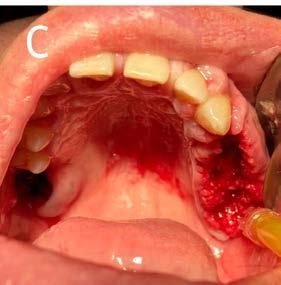

Descripción del caso

Paciente masculino de 45 años de edad, acude a consulta dental a la Clínica Integral de Ciencias de la Salud de la Universidad Autónoma de Baja California en la ciudad de Tijuana, manifiesta tener dolor, sangrado e inflamación generalizada en las encías, en su historia clínica comenta ser hipertenso desde

Figura 3. Fotografías intraorales.

hace 8 años por lo que toma 30 mg de nifedipino cada 12 horas, amlodipino 5 mg cada 24 horas, telmisartan 40 mg cada 12 horas y metropolol 100 mg cada 12 horas, además comenta padecer diabetes mellitus tipo II desde hace 7 años por lo que también toma 50 mg de metformina cada 12 horas y dapagliflozina 10 mg cada 24 horas. Clínicamente se observó una encía roja y sangrante, profundos sondeos, una notable hiperplasia gingival, depósitos de cálculo y movilidad dental grado III en todos los órganos dentarios a excepción del segundo premolar superior derecho al canino superior izquierdo, quienes presentaban una movilidad grado II. Radiográficamente se encontró una pérdida de inserción radiográfica avanzada generalizada

Figura 4. Raspado y alisado radicular de órganos dentarios con posibilidad de mantenerse en boca.

en la arcada inferior, y grupos molares de ambos cuadrantes superiores (Figura 1), los únicos órganos dentarios con posibilidad de preservación en boca a través de terapia periodontal se encontraron en el sector anterior de la arcada superior anteriormente mencionados con movilidad grado II

(Figura 2). Por lo que se diagnostica con periodontitis generalizada, estado IV, grado C (Figura 3).

Por lo anterior se decidió iniciar con instrucciones de higiene oral, raspado y alisado radicular en aquellos órganos dentarios que se mantendrían

Figura 5. Modelos de estudio, registro de mordida y bases y rodillos.

Figura 6. Prótesis inmediatas terminadas.

7. A) Extracción de órganos dentarios sin salvación. B) Legrado alveolar. C) Exéresis de tejido hiperplásico.

D) Sinéresis de los tejidos.

en función en boca (Figura 4) y planificar el tratamiento a través de un proceso protésico-quirúrgico, el cual consistiría en la elaboración de prótesis inmediatas, pues debido a la gran

destrucción de los tejidos de soporte de los dientes remanentes sería necesario realizar extracciones múltiples de aquellos órganos dentarios sin salvación, todo esto con la finalidad de

Figura 8. Prótesis inmediatas adaptadas a los rebordes alveolares residuales.

Figura

aportarle al paciente beneficios estéticos y psicológicos para eventualmente transicionar a una rehabilitación protésica definitiva.

Para la elaboración de las prótesis inmediatas se realizaron modelos de estudio de la boca del paciente, un registro de mordida con silicona de adición a base de polivinilsiloxano y se realizaron bases y rodillos en las zonas edéntulas que permitieran registrar la dimensión vertical en oclusión del paciente (Figura 5), posteriormente se envió el trabajo al laboratorio dental y se obtuvieron las prótesis inmediatas para ser insertadas durante la etapa quirúrgica (Figura 6).

Posteriormente se abordó la fase quirúrgica: se realizaron las extracciones de los órganos dentarios sin posibilidad de mantenerse en función en boca, se efectuó el legrado alveolar para retirar tejido infectado, además de realizar la exéresis del tejido hiperplásico, y regularización ósea para posteriormente producir la sinéresis de los tejidos a través de una sutura continua simple con sutura absorbible Vicryl 3-0 (Figura 7).

Concluida la intervención quirúrgica se efectuó la inserción de las prótesis inmediatas previamente fabricadas colocando acondicionador de tejidos Softy Autocurable NicTone al interior

Figura 9. A) Fotografías intraorales a la semana de la intervención quirúrgica. B) Fotografías intraorales a las 2 semanas de la intervención quirúrgica.

La destrucción de los tejidos de soporte no solo ocasiona la pérdida de dientes y hueso alveolar, la condición periodontal con ausencia de tratamiento puede empeorar la ya establecida y la infección se puede extender a otros órganos o sistemas de órganos, por lo que es de vital importancia tratar de evitar en pacientes sistémicamente comprometidos y farmacodependientes.

de ambas prótesis y adaptándolas a los rebordes alveolares residuales (Figura 8).

Finalmente se realizaron citas de control para retirar las suturas y supervisar la correcta cicatrización de los tejidos y readaptación de las prótesis inmediatas a la primera y segunda semana posteriores a la intervención quirúrgica (Figura 9). Se introdujo al paciente a un sistema de revisiones periódicas para evaluar las condiciones de los tejidos y eventualmente transicionar a una rehabilitación protésica definitiva.